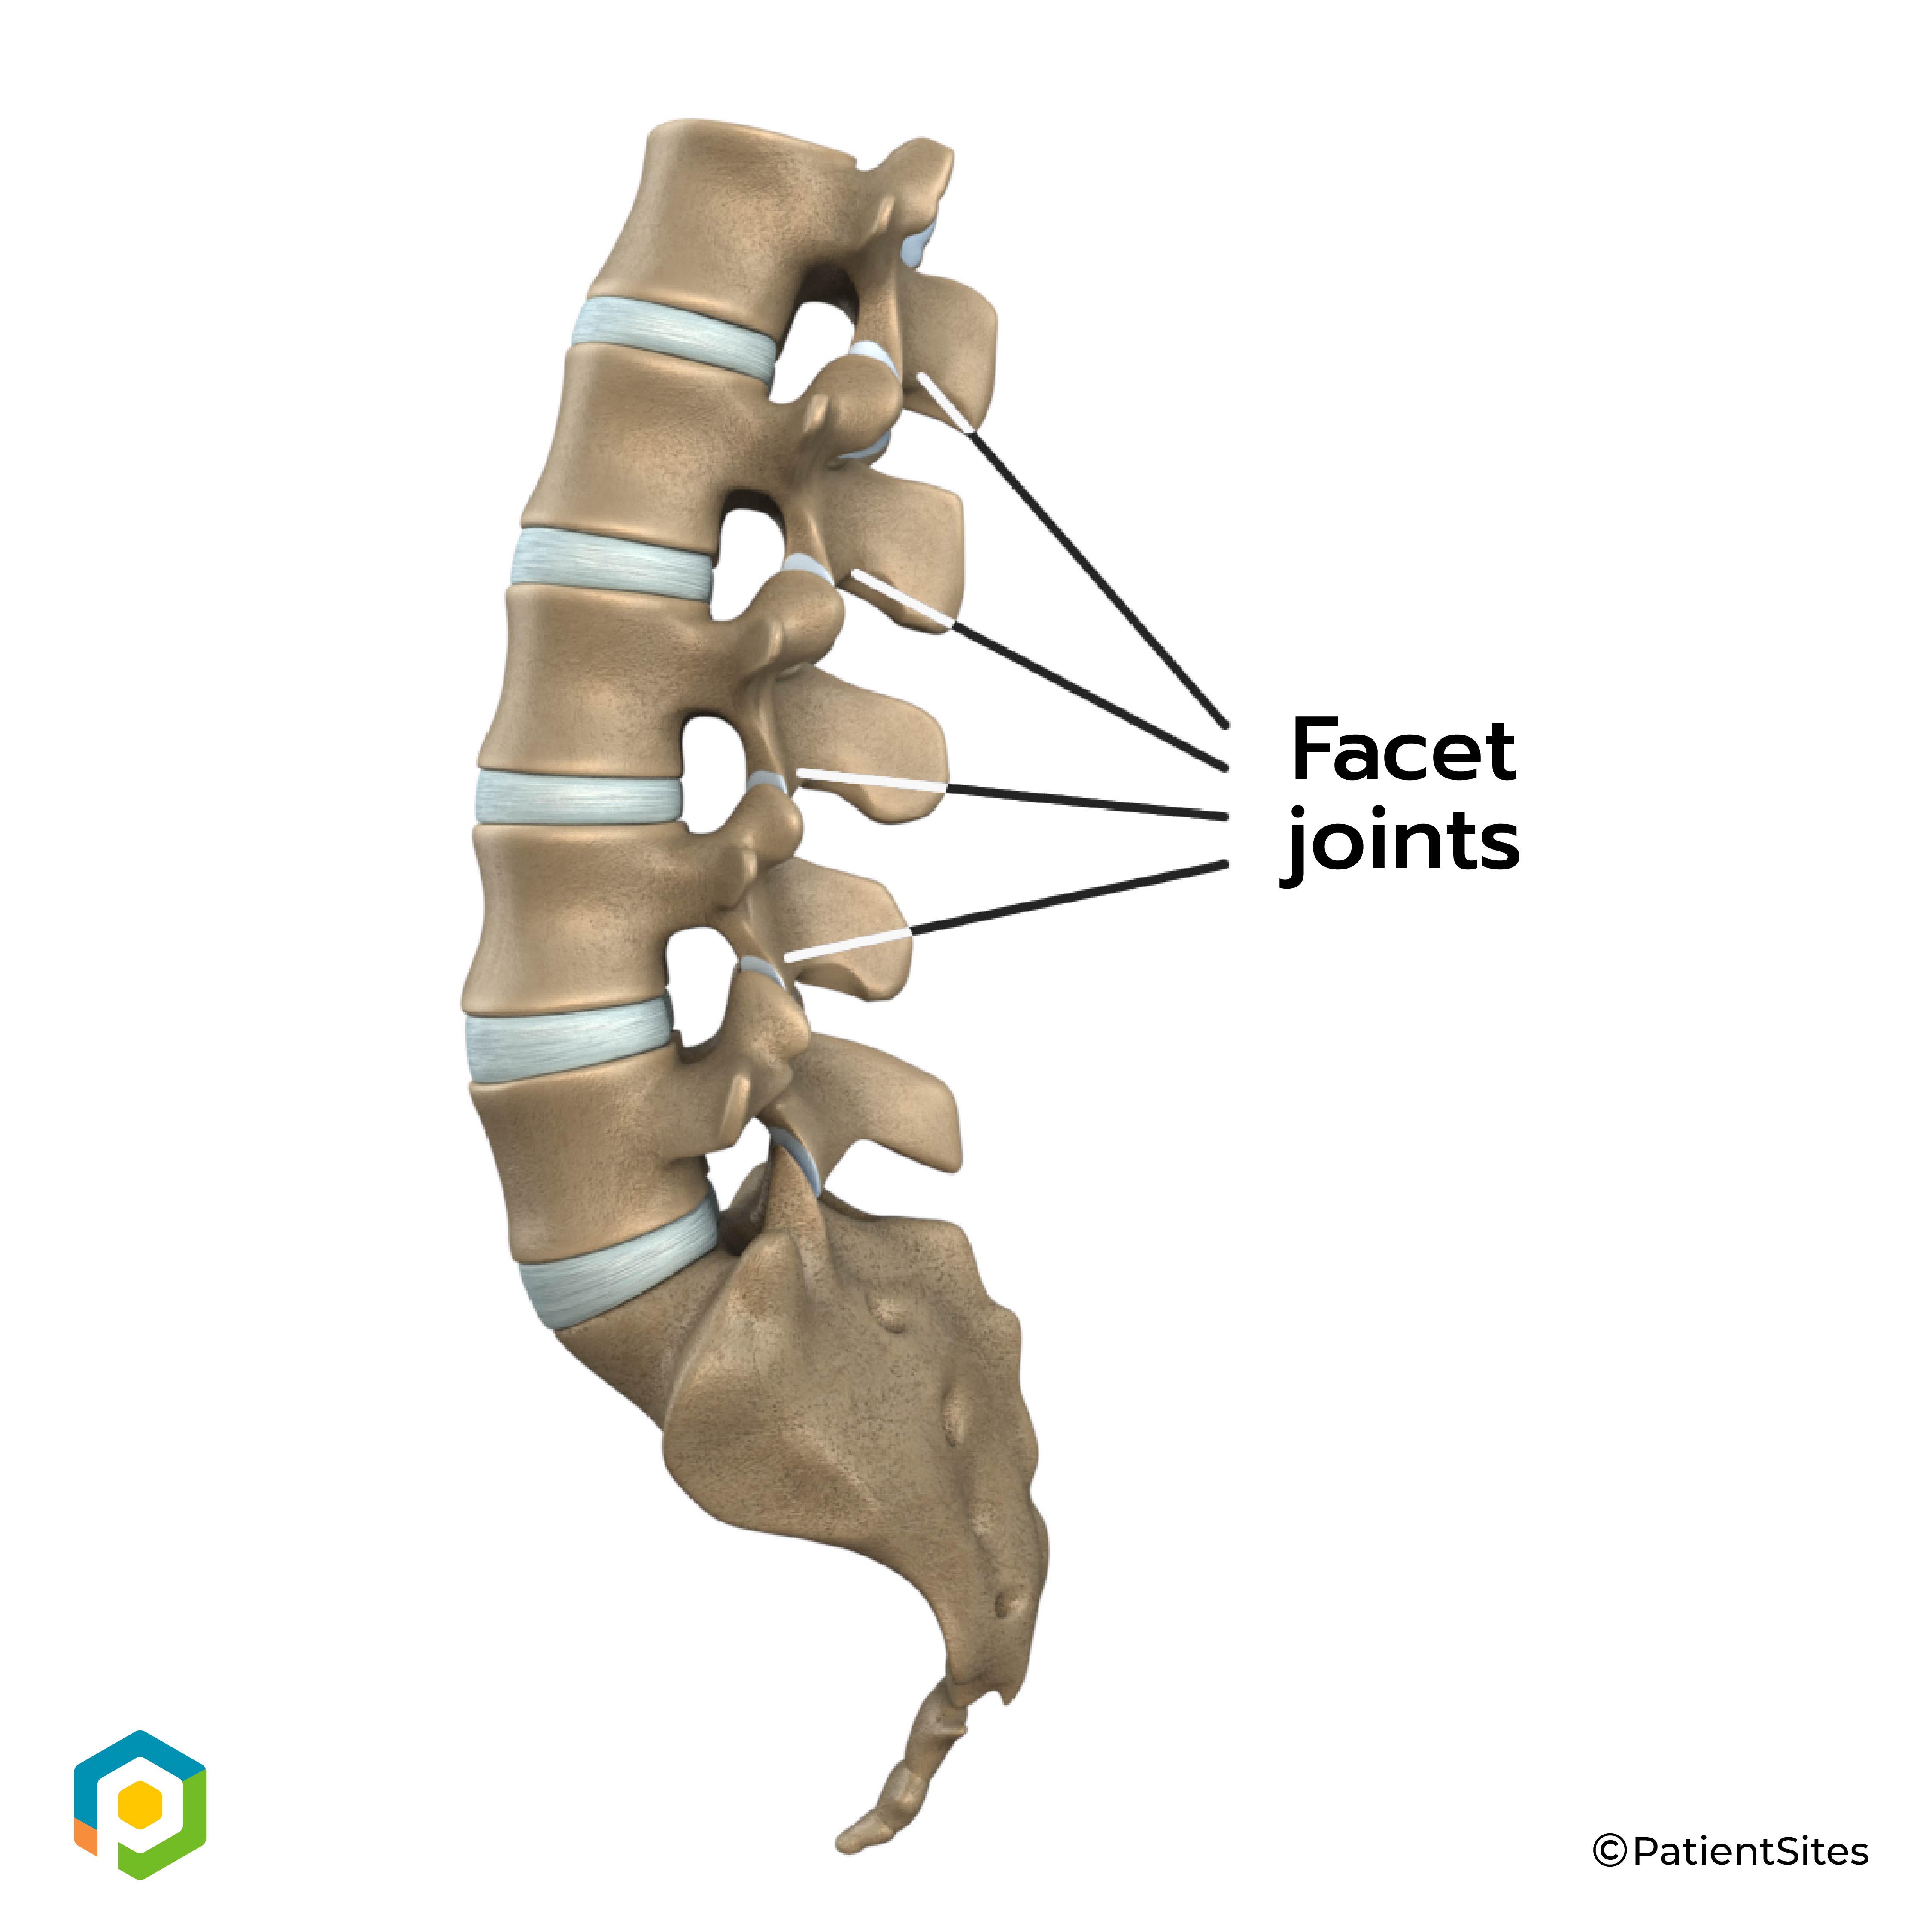

Between the vertebrae of each spinal segment are two facet joints. The facet joints are located on the back of the spinal column. There are two facet joints between each pair of vertebrae, one on each side of the spine. A facet joint is made of small, bony knobs that line up along the back of the spine. Where these knobs meet, they form a joint that connects the two vertebrae. The alignment of the facet joints of the lumbar spine allows freedom of movement as you bend forward and back.

Facet Joints